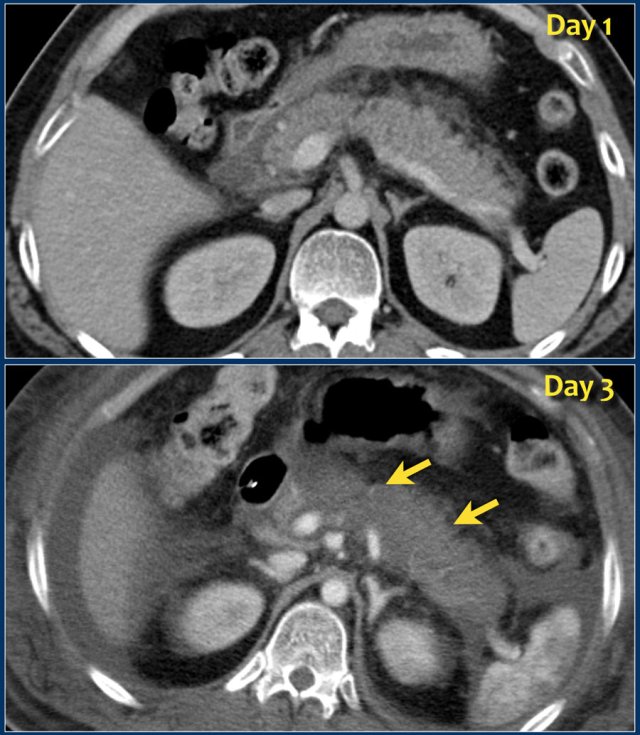

An early CT may be misleading regarding the morphologic severity of the pancreatitis, because it may underestimate the presence and amount of necrosis.

The images show a normally enhancing pancreas on day 1.

As the patient's condition worsened, a second CT was performed on day 3.

Notice how the greater part of the pancreatic body and tail no longer enhances indicating necrotizing pancreatitis (arrows).

The first CT underestimated the severity of the pancreatitis.

This patient died on day 5 due to severe SIRS and multiple organ failure.